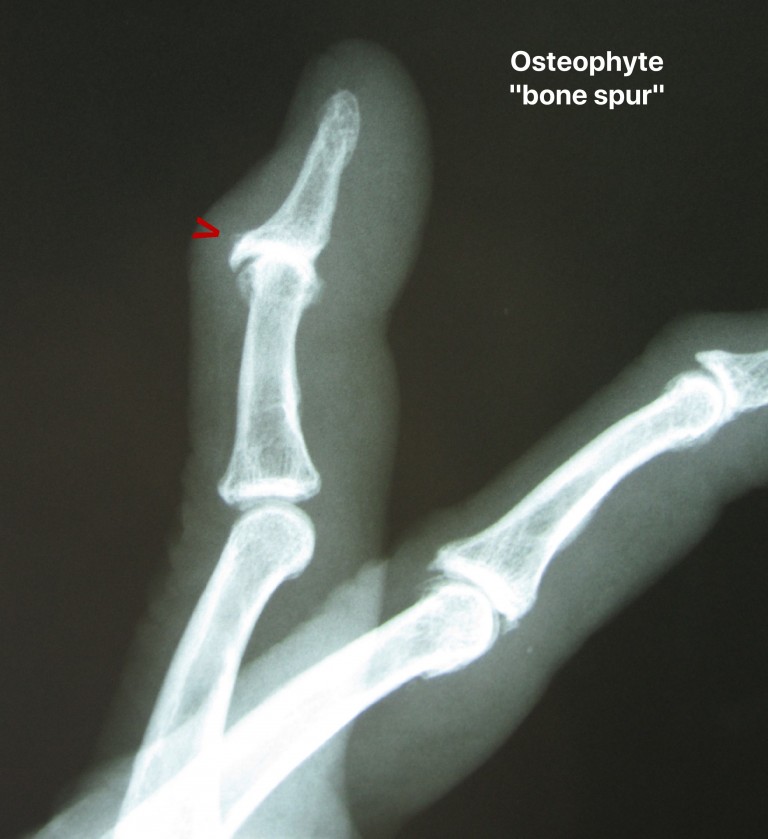

Digital mucus cyst. (A) Lateral radiograph of index finger demonstrates Gel Cyst Finger Here, find out how to recognize and treat them. A digital myxoid pseudocyst is a shiny papule found at the end of a finger or toe, close to the nail. They are associated with osteoarthritis (oa) and usually develop in patients 50 to 70 years old. It’s also called a digital mucous cyst or mucous pseudocyst. A myxoid cyst is. Gel Cyst Finger.